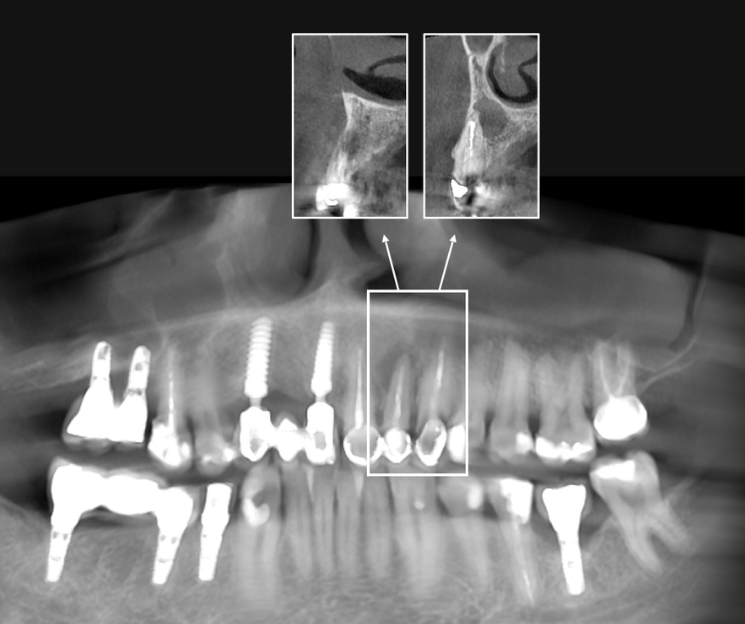

Paciente con infecciones de origen dental que comprometían severamente el hueso alveolar en la zona anterior superior. Se realizó la extracción de los dientes 21, 22 y 23, y se optó por una rehabilitación inmediata mediante implantes córticobasales.

Esta combinación permitió anclar los implantes en hueso cortical, que mantiene su estabilidad incluso en presencia de procesos infecciosos en el hueso alveolar. El resultado: rehabilitación funcional y estética el mismo día de la cirugía.